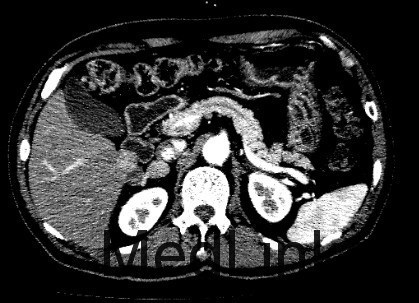

查体: 左上腹外侧见手术切除,余无异常。 辅助检查: 1、检验 白细胞WBC 6.15x10^9/L,血红蛋白Hb 165 g/L,血小板PLT 173x10^9/L;乙肝表面抗原HBsAg(-),乙肝核心抗体HBcAb(+);AFP, CEA、CA125、CA19-9均正常范围 2、影像学 CT:肝S6内缘包膜下结节(19×17mm、19×19mm,),考虑肝细胞癌可能性大,建议进一步检查;其相邻低密度结节,不除外肝囊肿。 2.右侧肾上腺结节,考虑转移瘤可能性大。 3.双肾囊肿。

临床诊断 肝细胞癌 治疗: 手术切除右侧肾上腺转移瘤和右肝肿瘤 术后病理: 1、(肝)送检4x3x2cm灰褐色组织一块,切面灰黄,质软。 镜下:送检肝组织内见境界较清楚的胶原纤维包裹的坏死结节,其内可见肿瘤残影,建议结合临床患者是否行介入等治疗,则可符合治疗后改变,未见残留肿瘤细胞。另一组织提示增生的肝细胞Glypican-3灶性(+),CD34显示增生的结节毛细血管化。 特殊染色:网状纤维染色显示肝细胞索增生。 结合HE形态及免疫组化结果,病变符合肝细胞癌。 2(肾上腺结节)送检5x3x3cm淡黄组织一块,可见直径2cm灰白结节。 镜下:肾上腺组织内见肝细胞癌浸润。